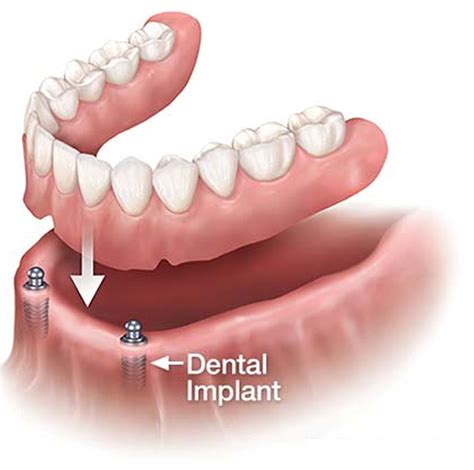

Over denture implants are a type of dental implant that supports a denture, providing a more secure fit compared to traditional dentures. These implants are surgically placed into the jawbone and act as anchors for the denture, preventing it from slipping or moving out of place. This stability enhances the overall comfort and functionality of the denture, allowing patients to enjoy their favorite foods and speak with confidence.

The next step is the surgical placement of the implants. This procedure is usually performed under local anesthesia. The dentist will make small incisions in the gum tissue to expose the jawbone and then place the implants into the bone. The gums are then sutured closed, and the implants are allowed to heal and integrate with the bone over a period of several months.

Once the implants have fully integrated with the jawbone, the dentist will attach the denture to the implants. For ball-retained implants, the dentist will place the ball-shaped attachments onto the implants and fit the denture with corresponding sockets. For bar-retained implants, the dentist will attach a thin metal bar to the implants and fit the denture with a corresponding attachment.